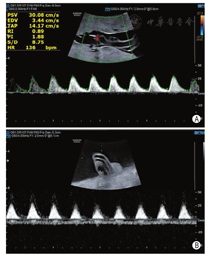

孕妇38岁,孕1产0,既往体健,无家族史及个人病史,无近亲结婚史。孕早期超声检查、孕23周系统超声检查胎儿结构均未见异常。孕30+4周超声检查:脐动脉收缩期峰值流速(Vs)与舒张末期血流流速(Vd)比值(S/D)4.0,搏动指数(PI)1.42,阻力指数(RI)0.64;偶测及脐动脉舒张期血流消失。孕31+2周超声检查:脐动脉S/D 4.83,PI 1.79,RI 0.79。孕31+5周超声检查示脐动脉舒张期血流消失。孕32+4周超声检查:脐带胎盘插入处可见纤细隔样回声,长5.4 cm,一端与胎盘子面相连,一端与脐带相连,与脐带关系密切,扫查期间内未见两者分离(图1A,图1B)。脐动脉均可测及血流信号,其一内径0.45 cm,收缩期峰值流速(PSV)30.08 cm/s,S/D 8.75,PI 1.88,RI 0.89(图2A);其二内径0.25 cm,舒张期血流消失(图2B)。胎儿大脑中动脉PSV 29.65 cm/s,S/D 4.60,PI 1.60,RI 0.78。超声提示:脐动脉血流异常,脐带根部羊膜带回声,不除外与脐带粘连。孕33+1周行剖宫产证实羊膜带缠绕脐带根部,脐带受压(图3)。新生儿1 min Apgar评分9分(肌张力-1分),5 min、10 min Apgar评分均为10分。

羊膜带综合征是部分羊膜破裂产生纤维带,粘连缠绕胚胎或胎儿而形成的一种畸形,目前认可度较高的病因假说为1965年Torpin等[1]提出的外因论:妊娠早期羊膜破裂而绒毛膜尚完整,羊水通过破裂口外渗入绒毛膜腔导致羊水一过性减少,胎儿与羊膜绒毛膜面贴近,羊膜表面的中胚叶绒毛组织具有增生、浸润能力,可产生纤维带缠绕并破坏胎儿或附属物,导致相应部位畸形,最常见的是形成四肢缩窄环,偶有羊膜带缠绕脐带导致脐带受压甚至闭锁,造成胎儿宫内窘迫,严重的可致胎死宫内[2]。本例羊膜带缠绕脐带超声表现为2条脐动脉粗细不一,脐动脉血流异常,且因受压程度不同而出现相应的改变,即在较粗的脐动脉取样时测得脐动脉S/D、PI、RI均升高,而在较细的脐动脉取样时脐动脉舒张期血流消失。